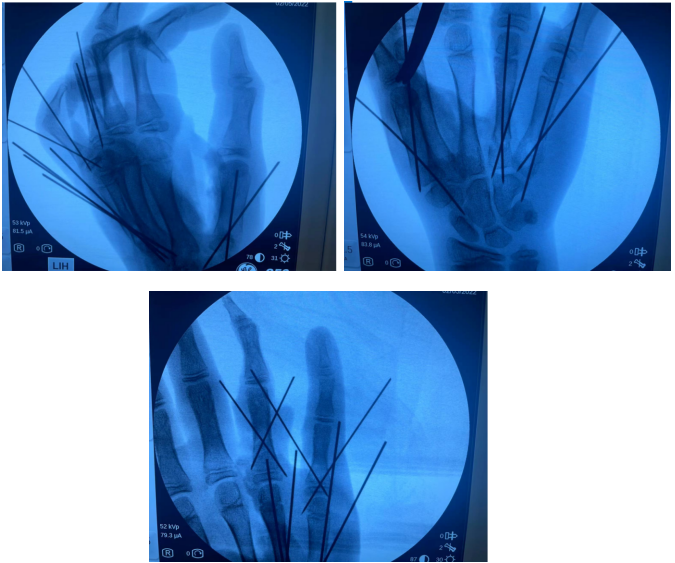

术中X片